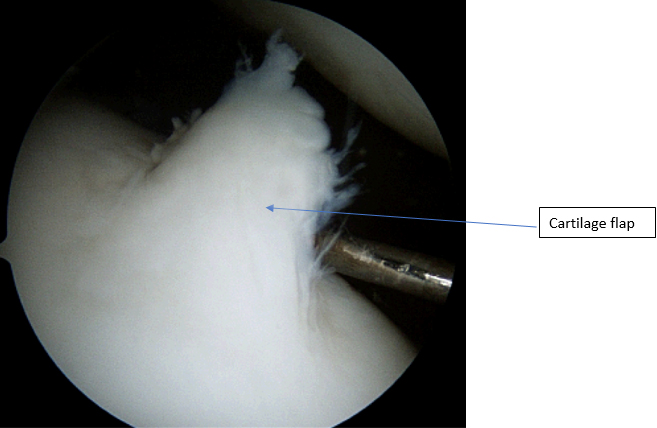

When there is damage to the cartilage the joint may not run smoothly which can cause pain and stiffness. Further to this if there is a loose flap of cartilage it can catch in the knee or jam in the knee giving sharp pain or a feeling of the knee getting stuck.

When the cartilage damage is small or where the primary aim is to return to activity ASAP then arthroscopic removal of the loose or damaged cartilage would often be undertaken.(See arthroscopy)